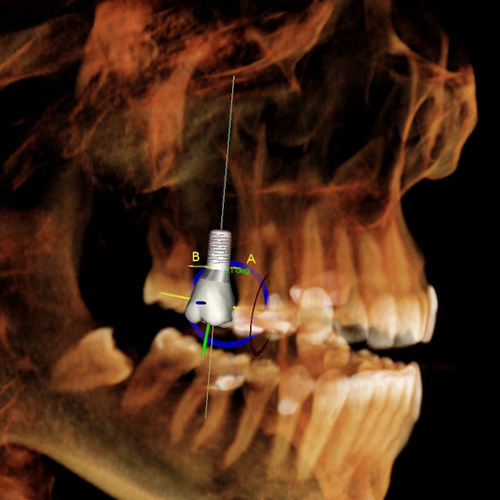

Damage to the inferior dental nerve (NDI)

The dental nerve runs through the lower jaw. When placing a traditional implant, there is a risk of damage to this nerve when drilling with a large diameter. The results can be very inconvenient for the patient. Paralysis or loss of feeling on one side of the face, lips, and teeth. Sometimes the nerve may simply have been affected without being damaged. In this case, the loss of feeling is temporary.

Perforation of the sinus during the placement of the dental implant

Perforation of the sinus is rare and is not necessarily due to a bad act of the dentist. Bone tissue is not a flat surface but irregular and the nerve can sometimes have bifurcations. Drilling in traditional implantology is wide and the margin of error less important. Sinus perforation can be managed quite easily but requires several visits.